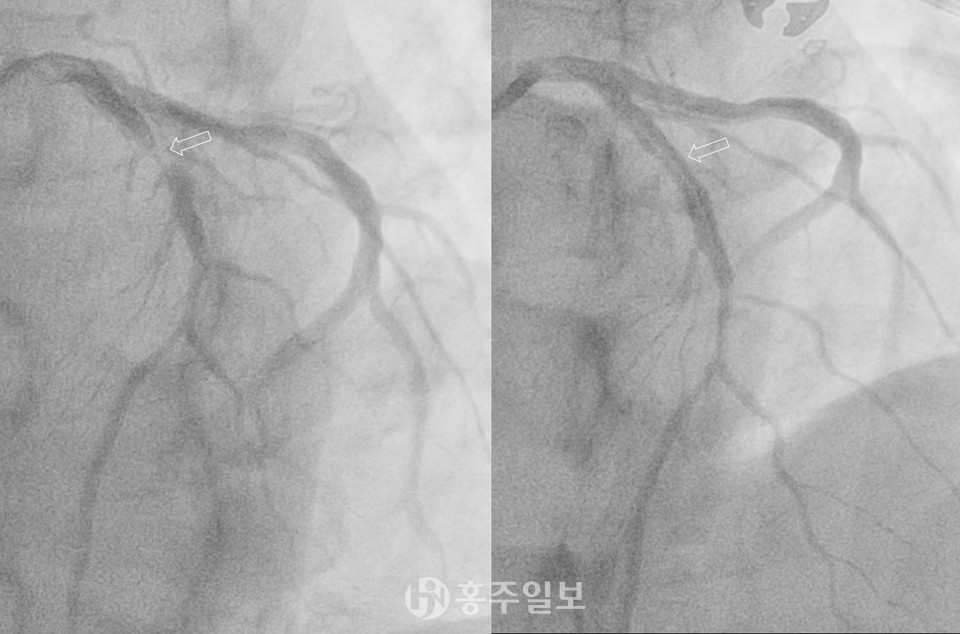

전 세계 사망 원인 1위, 국내 사망 원인 2위에 해당하는 치명적인 질환인 심혈관질환, 그중 관상동맥 질환이 대표적이다. 관상동맥이 좁아지면 협심증이 발생하고, 좁아진 상태에서 염증 파열 등으로 갑자기 혈관이 막히면, 심장 근육이 손상되는 심근경색으로 이어질 수 있다.

특히 대학병원급의 최신 CT는 심장질환 진단의 정밀도를 크게 높여 관상동맥질환을 조기에 진단할 수 있는 중요한 도구로 자리 잡았으며, 지역 내에서 심혈관질환의 조기 발견 사례가 증가하고 있다.